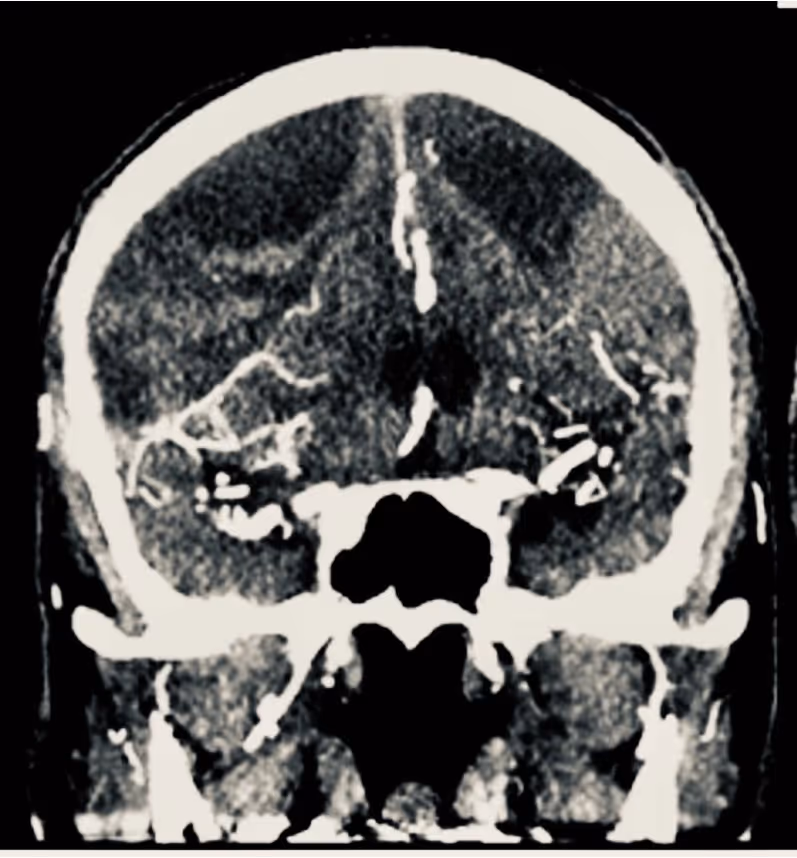

Understanding Brain Arteriovenous Malformations (AVM)

What is an AVM? How do they develop?